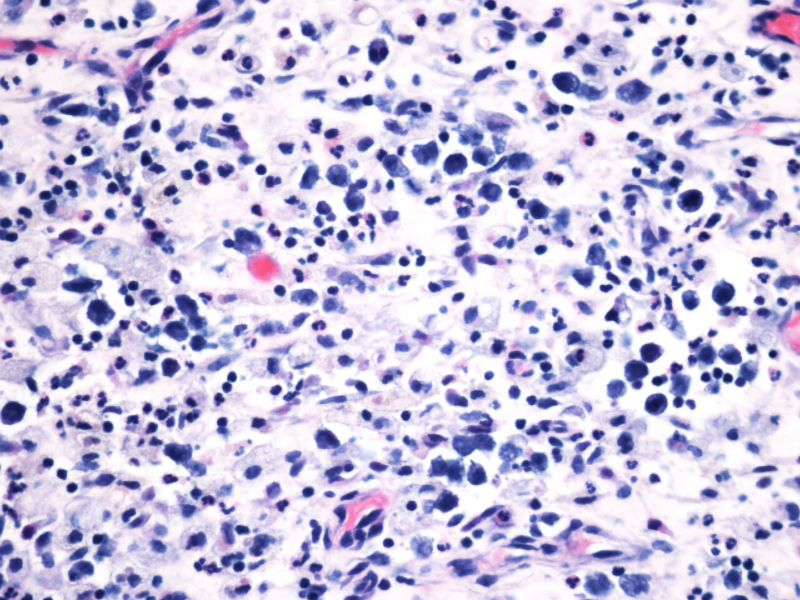

ALK阳性ALCL发病年龄,发病部位,细胞形态可以非常广泛。西方国家统计男女比例为1.5:1,主要是40岁以内,尤其是儿童青少年多发。本例46岁女性,流行病学应少见的女性发病时段;

如金老师所言原发于骨也少见,如标题所显示:“临床骶骨脓肿?”表现为骨脓肿恐怕更少,综合以上所以本例的确特殊;

形态学hallmark 细胞显示不是很清晰,大的肿瘤细胞如果在ALCL和HL之间选择可能不容易,但HL的肿瘤细胞形态学特点的范围比较狭窄,而ALCL可能具有更广泛的形态学范围,细胞大小形态以及典型hallmark cell的多少有时很难确定。如果只看HE,觉得ALCL的可能会安全一点,当然我个人经验不足,可能理解得比较肤浅。

的确如此,CD43不仅表达于多量T细胞淋巴瘤,还可以表达于一些B细胞淋巴瘤,如套细胞淋巴瘤、小淋巴细胞淋巴瘤/白血病、粒细胞肉瘤等等,甚至还可以表达于一些非肿瘤细胞。本例CD2,CD3,CD4,CD8,CD5,CD7均阴性,在这样的大细胞病变形态基础上,此时做CD43和细胞毒标记物只是寻找诊断ALCL的佐证,后来果然CD43和部分细胞毒标志物是阳性,对于“裸”免疫表型的ALCL,这一诊断思路也是WHO和许多文献推荐的,日常工作中也是我们也常常是这样做的。如果病变是在淋巴结内,HE是大细胞病变,且出现上述免疫表型,我想应该有许多病理医生就诊断了ALCL了。只是本例部位等临床特征特殊,诊断需要慎之又慎,但最后ALK-1也显示大细胞阳性,就增加了诊断的信心。